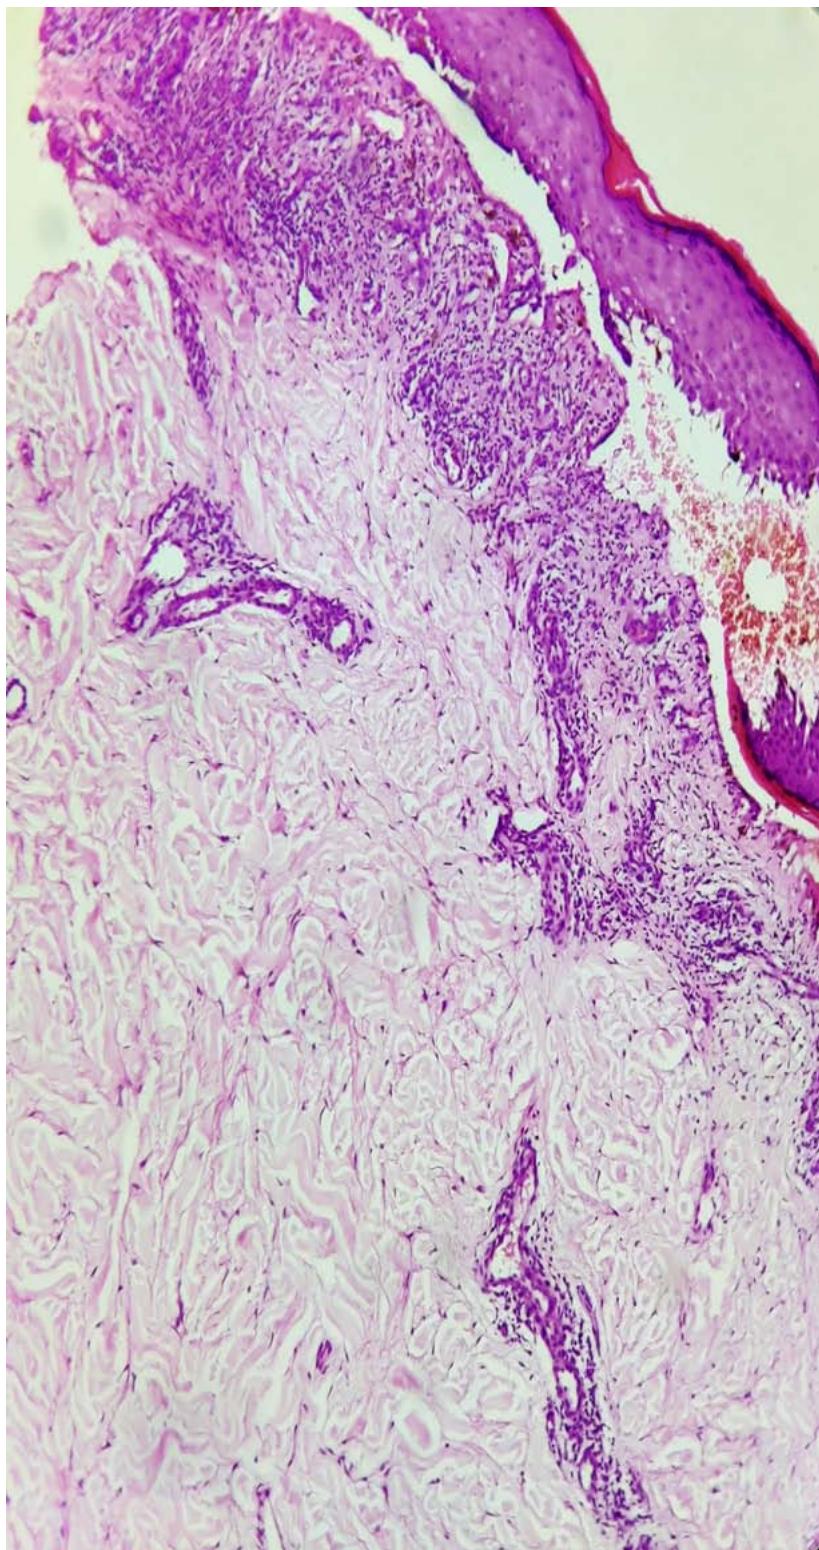

A 14-year-old female presented with multiple dark coloured, itchy lesions on legssince5 months. On examination, multiple violaceous papules to plaques of varying sizes (1cm - 5cm) were present on the extensor aspects of legs, forearm and dorsum of feet bilaterally. (Figs 1-3). Skin biopsy from the lesion showed hyperkeratosis, hypergranulosis, vacuolar degeneration of basal layer, band of dense lymphocytic inflammatory infiltrate in the papillary dermis, with perivascular histiocytic infiltrate confirming the diagnosis of lichen planus (LP) (Fig 4,5). She was started on topical corticosteroids, antihistamines and emollients. After 3 months patient had aggravation of LP with patchy hair loss over the scalp. On examination multiple, smooth alopecic patches of varying sizes, the largest being $4 \times 3 \mathrm{~cm}$, were noticed on the scalp. She was diagnosed clinically as alopecia areata (AA) (Fig 6). Investigations like complete blood count, liver function test, thyroid profile, anti-nuclear antibody, rheumatoid arthritis factor, C-reactive protein, ESR, VDRL, HBV, HCV, urine microscopy were normal. In view of progressing lesions of LP and AA, she was started on oral mini pulse therapy-betamethasone 5 mg twice weekly and was advised for follow-up. Good response was noticed by four weeks withresolution of LP and regrowth of hair over few patches.

Figure 5: Photomicrograph showing hyperkeratosis, parakeratosis, hypergranulosis, artifactual cleft formation between epidermis and papillary dermis (Max Joseph space), band of dense lymphocytic inflammatory infiltrate, histiocytes admixed with congested blood vessels, along with periadnexal inflammatory infiltrate. (H & E, x 10).